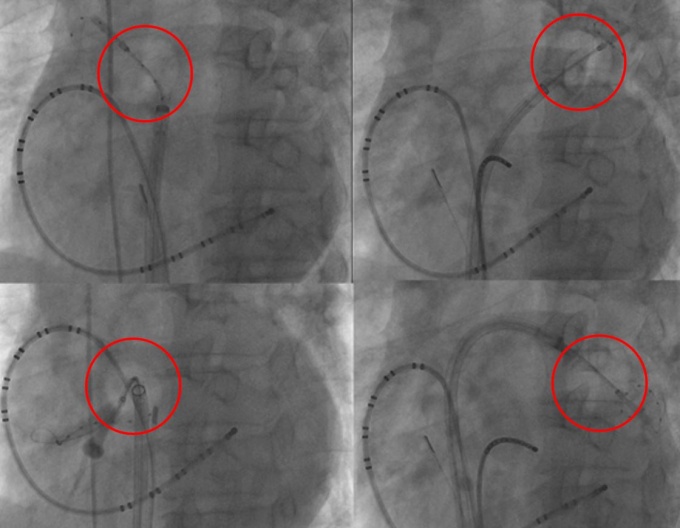

°Ç±¹´ëº´¿ø, ½É¹æ¼¼µ¿ ³Ã°¢ µµÀÚ ÀýÁ¦¼ú µµÀÔ

[µ¥Àϸ®¸Þµð ¹ÚÁ¤¿¬ ±âÀÚ] °Ç±¹´ëº´¿øÀº ½É¹æ¼¼µ¿ Ä¡·á¹ýÀÎ ³Ã°¢ µµÀÚ ÀýÁ¦¼úÀ» ½ÃÀÛÇß´Ù°í 6ÀÏ ¹àÇû´Ù.

½É¹æ¼¼µ¿Àº Á½ɽǰú ¿¬°áµÇ´Â ÆóÁ¤¸Æ ¾ÈÂÊ¿¡¼­ ºü¸£°í ºÒ±ÔÄ¢ÇÑ Àü±â¿¡ ÀÇÇØ ¹ß»ýÇÑ´Ù. ½É¹æ¼¼µ¿ Ä¡·á´Â ÀÌ ºÎÀ§ÀÇ Á¶Á÷À» ±«»ç½ÃÄÑ Á½ɹæÀÌ Àü±â½ÅÈ£¿¡ ¿µÇâÀ» ¹ÞÁö ¾Ê°Ô ÇÏ´Â ¿ø¸®·Î ÀÌ·ïÁø´Ù.

³Ã°¢ µµÀÚ ÀýÁ¦¼úÀº ÆóÁ¤¸Æ ÀÔ±¸¸¦ dz¼±À¸·Î ¸·Àº ÈÄ ÆóÁ¤¸Æ ÀÔ±¸Àüü¸¦ ¿µÇÏ 6~60µµ·Î ¾ó·Á ÀÌ ºÎÀ§ Á¶Á÷À» ±«»ç½ÃŰ´Â ¹æ½ÄÀÌ´Ù.

±âÁ¸ Ä¡·á¹ýÀÎ °íÁÖÆÄ µµÀÚ ÀýÁ¦¼ú°ú È¿°ú´Â ºñ½ÁÇϸ鼭µµ ½Ã¼ú ½Ã°£Àº 2½Ã°£ À̳»·Î, Àý¹Ý ÀÌ»óÀÇ ½Ã°£À» ´ÜÃà½ÃŲ °ÍÀÌ ÀåÁ¡ÀÌ´Ù.

°Ç±¹´ëº´¿ø ºÎÁ¤¸Æ Ŭ¸®´Ð ±ÇâÈñ ±³¼ö´Â “°íÁÖÆÄ µµÀÚ ÀýÁ¦¼úÀº ÆóÁ¤¸Æ ÀÔ±¸ Á¶Á÷À» ÇÑ Á¡, ÇÑ Á¡ ±«»ç½ÃÄѳª°¡´Â ¹æ½ÄÀ¸·Î ½Ã°£ÀÌ ¿À·¡ °É¸®´Â ¹Ý¸é, ³Ã°¢ µµÀÚ ÀýÁ¦¼úÀº ³Ã°¢ dz¼±À» ÆóÁ¤¸Æ ÀÔ±¸ Àüü¿¡ ¹ÐÂø½ÃÄÑ ÇÑ ¹ø¿¡ ³Ã°¢Ç졒ʱ«»ç½Ã۱⠶§¹®¿¡ ½Ã¼ú½Ã°£À» ´ÜÃàÇÒ ¼ö ÀÖ´Ù”°í ¼³¸íÇß´Ù.

ÇÑÆí, °Ç±¹´ëº´¿øÀº ºÎÁ¤¸Æ Ŭ¸®´ÐÀº ³Ã°¢ µµÀÚ ÀýÁ¦¼ú½ÃÇà¿¡ À̾î ÃֽŠ3Â÷¿ø½ÉÀ念»óÀåºñ¸¦ ÃÖ±Ù µµÀÔÇϴ µî °í³­µµ ºÎÁ¤¸Æ Ä¡·á È¿°ú¸¦ ³ôÀ̰í ÀÖ´Ù.